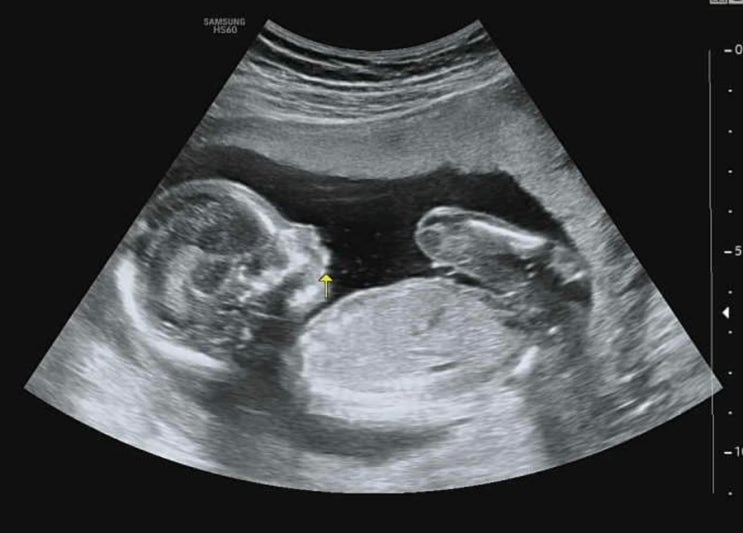

8. 대구 수성구 효성병원(#8. 19주 3일 초음파진료) 및 보험적용안내 후기

2024년 6월 27일 목요일 - 17주 세컨 병원에서 빤짝이 만나고 왔었는데 분만병원 정기적으로 가는날! ㅎㅎ ...

2024년 6월 11일 화요일 - 15주에 병원을 다녀왔었고 4주뒤인 19주에 정기진료일이나... 잘있는지(당연히 ...